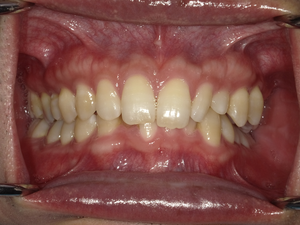

☆before→after☆◯ご相談内容:歯の叢生◯矯正の種類:マウスピース型矯正「インビザラインGO」◯治療期間:10週間◯治療費用:44万円(税込)